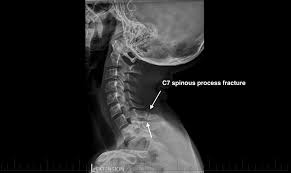

A transverse process fracture at the level of l5 is a surrogate marker of vertical instability of the pelvic fracture due to the attachment of the iliolumbar ligaments. Possible causes, signs and symptoms, standard treatment options and means of care and support. Transverse processes are used as lever arms by the deep spinal muscles to maintain posture and to induce rotation and lateral bending. It may occur as an avulsion fracture due to strong contracture of the muscles. Although the fracture is not associated with spinal cord damage and neurological deficits, the extreme force of the injury can cause visceral injuries and internal hemorrhage. The presence of other injuries might also be assessed due to the level of force needed to break the transverse process. In 78% of transverse process fractures, ct scanning showed that the fracture extended into the transverse foramen. Transverse process fractures caused by stress are likely under detected since even an acute transverse process fracture requires a high index of suspicion to be correctly identified(4,7). Here is an example of a patient with a benign looking transverse process fracture with an associated significant injury to the back. Transverse process fracture you have fractured a transverse process. Thoracic transverse process fractures (ttpfs) are injuries that go unnoticed during traditional autopsies, as demonstrated by a lack of medicolegal publications regarding ttpfs. We retrospectively reviewed the reports of lumbar spine and abdominopelvic ct scans from 2017 and 2018 to classify the types of spine fractures, their mechanism of injury, treatment and. Up to 60% of lumbar transverse process fractures identified on ct will be missed on plain radiographs.

The transverse foramen is an opening on each of the transverse processes of the cervical spine which gives passage to the vertebral artery and vein and a sympathetic nerve plexus. There are two transverse processes that extend off each vertebra in the details: Transverse process fractures are common sequelae of trauma, although they are considered a minor and stable lumbar spine fracture. Transverse processes are typically fractured in direct blows from athletics touch or impact from falls from bikes/motorbikes or by heights. However, postmortem computed tomography (pmct) has made detection of this type of injury easy. There are two transverse processes that extend off each vertebra in the spine, one on each side. A transverse process fracture is a break in 1 or more transverse process. In 78% of transverse process fractures, ct scanning showed that the fracture extended into the transverse foramen. A transverse process fracture is considered as a rare injury. A transverse process fracture is a break in 1 or more transverse process. What is a transverse process fracture? Transverse process fractures caused by stress are likely under detected since even an acute transverse process fracture requires a high index of suspicion to be correctly identified(4,7). If ct confirms isolated injury lateral flexion/extension views are indicated to rule out dynamic instability.

However, postmortem computed tomography (pmct) has made detection of this type of injury easy. There are two transverse processes that extend off each vertebra in the details: What is a transverse process fracture? It may occur as an avulsion fracture due to strong contracture of the muscles. It occurs as a result of sudden and extreme trauma. If ct confirms isolated injury lateral flexion/extension views are indicated to rule out dynamic instability. Vertebral angiography, performed in eight patients with fractures involving the transverse foramen, showed dissection or occlusion of the vertebral artery in seven (88%) instances. This part extends out from the side of the main body of the bone (called the vertebral body). A transverse process fracture at the level of l5 is a surrogate marker of vertical instability of the pelvic fracture due to the attachment of the iliolumbar ligaments. We retrospectively reviewed the reports of lumbar spine and abdominopelvic ct scans from 2017 and 2018 to classify the types of spine fractures, their mechanism of injury, treatment and. Up to 60% of lumbar transverse process fractures identified on ct will be missed on plain radiographs. In 78% of transverse process fractures, ct scanning showed that the fracture extended into the transverse foramen. Transverse process fractures identified on helical computed tomography (ct) scans without the presence of any other fracture or.